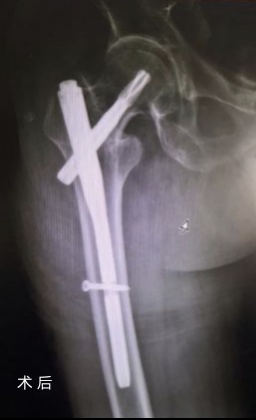

在完善各项术前准备后,刘波副教授团队为老人行“右股骨转子间骨折切开复位内固定术”,全程在C臂透视引导下完成微创手术,手术用时仅40分钟,切口不足5cm,术中失血50ml。为最大程度缩短手术时间,医生身穿铅衣,全程在射线下进行手术,当他们脱下厚重的铅衣时,手术服已经被汗水浸透。微创手术、多模式疼痛管理以及术后快速康复护理模式的积极介入,老人术后恢复顺利。骨科人的严谨、专业、温暖得到了患者及家属的一致肯定与认同。